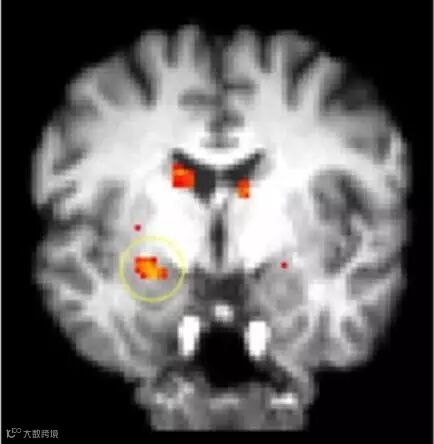

2006年,阿莫迪奥和同事派翠西德文请150名白人大学生给许多词语分类。类别包括令人愉悦的词语(如平静、天堂、荣誉)或令人不悦的词语(如癌症、呕吐、贫穷),智力相关的词语(如数学、聪明的、科学家)或体育相关的词语(如篮球、敏捷的、舞蹈)。在每个归类任务开始前,研究对象都会看见一张白人或黑人的脸庞。结果显示,被试大部分在看到黑人脸孔后,较快的归类了令人不悦的以及体育相关的词语;而看到白人脸孔后,则较快的归类了令人愉快的以及智力相关的词语,隐性偏见在结果中展露无遗。所以,大脑里究竟发生了什么,利用核磁共振成像发现,当被试看到他族人群的脸庞时,大脑的杏仁核部分会活跃起来,而这部分与恐惧适应学习有关。就像是小白鼠明白听到特定的铃声时,变灰受到一次电击。而我们的文化里充斥着与种族相关的各种刻板印象,所以对于跟我们长相差异的人,就会“学习”到不准确和充满偏见的信息,杏仁核就会高速运行。

▲隐性种族偏见研究中杏仁核活动的FMRI图